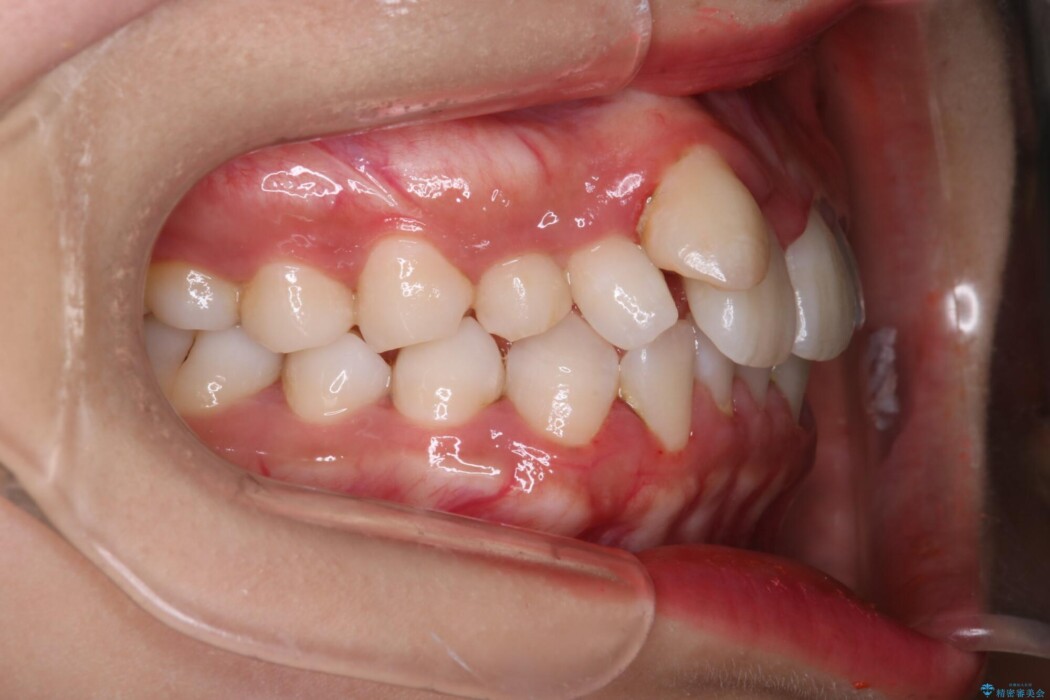

飛び出た上顎右側の八重歯が気になるとのことで来院されました。

上顎右側に乳歯が残っていることによって不正歯列(八重歯)となっているため、乳歯を抜歯してスペースを確保した上で、インビザラインによる八重歯の改善を行いました。

インビザラインをしっかり使用していただけたことにより、きれいな仕上がりとなりました。